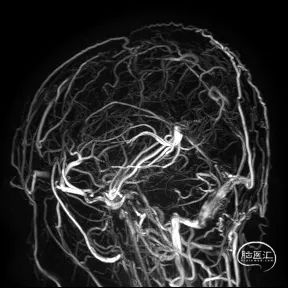

术前CTA/CTP检查,动脉成像未见明显异常,平扫CT可见右侧横窦区域高密度、左侧顶叶片状高密度,窦汇区域、上矢状窦区域高密度充盈。随后紧急性头颅MRV检查,MRV提示上矢状窦及右侧横窦区域不显影。

图注1:1A/1B 平扫CT可见右侧横窦、窦汇区域高密度,额顶叶片状高密度灶

1C 通路CTA检查动脉像未见特殊

1D/1E MRV冠状位及侧位可见上矢状窦及右侧横窦消失,左侧横窦乙状窦部分显影